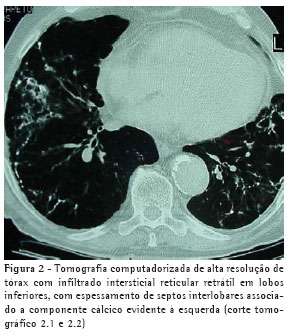

Um paciente do sexo masculino, de 75 anos de idade, ex-metalúrgico, tabagista de 50 maços-ano, procurou atendimento médico com dispnéia progressiva nos últimos quatro meses, que havia piorado havia uma semana e no momento do atendimento estava presente aos mínimos esforços. Relatava ainda dor torácica direita e tosse seca. Tinha antecedentes de diabetes melito, insuficiência renal crônica não dialítica, hipertensão arterial sistêmica e miocardiopatia isquêmica. Ao exame, apresentava-se dispnéico (freqüência respiratória de 30 incursões por minuto), taquicárdico (freqüência cardíaca de 120 batimentos por minuto), com estertores em velcro em bases, bulhas hipofonéticas e edema +/4+ em membros inferiores. A radiografia torácica (Figura 1) apresentou infiltrado intersticial retrátil em bases pulmonares, retificação de cúpulas frênicas com contornos mal-definidos, aumento difuso de transparência pulmonar em campos médios e superiores, imagem cardíaca aumentada, e aorta ectasiada e ateromatosa. A tomografia computadorizada de alta resolução do tórax (Figura 2) mostrou infiltrado intersticial reticular retrátil em lobos inferiores, com espessamento de septos interlobares associado a componente cálcico evidente à esquerda, enfisema centrolobular em lobos superiores, espessamento pleural esquerdo, aorta ectasiada e ateromatosa, e área cardíaca normal.